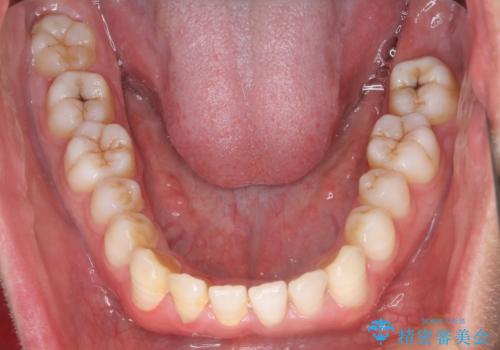

- 前歯のすきっ歯が気になると来院された患者様です。

前歯の隙間をマウスピース矯正(インビザライン)を使用して、閉じていきました。